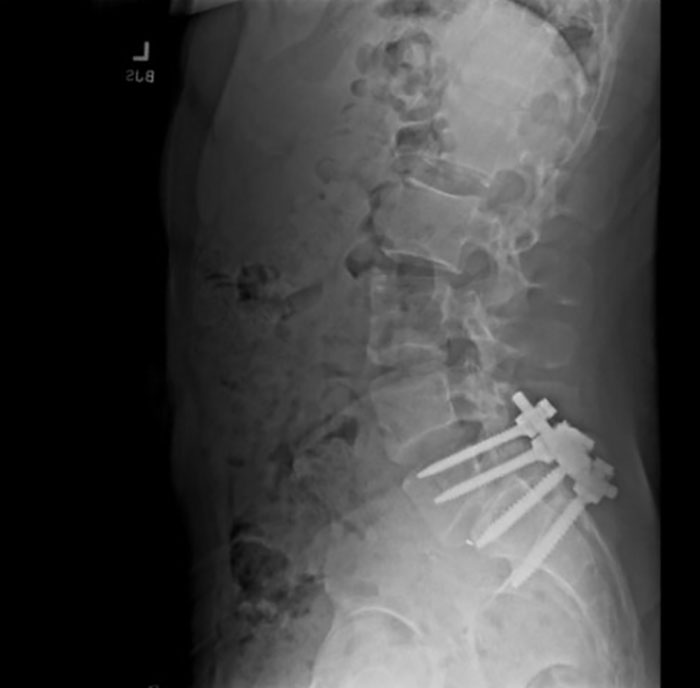

RJ, who lost touch with the alleged shooter, said one of the last text messages he received from him was an X-ray of his spine. Luigi said he underwent back surgery at the time.

It “looked heinous, with just giant screws going into his spine,” he said.

The Reddit posts indicated the physical pain the user underwent since childhood due to spondylolisthesis—a condition where one of the bones in the spine (called vertebra) slips out of place.

“He was posting an x-ray on his social media. Some of the writings that he had, he was discussing the difficulty of sustaining that injury,” Kenny was quoted telling Your World with Neil Cavuto.